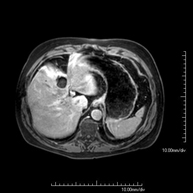

Prova diagnòstica no invasiva que consisteix en l'obtenció d'imatges d'alta definició anatòmica del fetge mitjançant l'ús d'un camp electromagnètic i ones de ràdio (amb un emissor i un receptor). No utilitza radiació ionitzant. Es realitza per estudiar qualsevol lesió localitzada en el fetge. Normalment es requereix l'ús de contrast paramagnètic (Gadolini) per caracteritzar les lesions. És necessari realitzat la prova en dejú (6 hores). - RM de Ronyons

Prova diagnòstica no invasiva que consisteix en l'obtenció d'imatges d'alta definició anatòmica d'ambdós ronyons mitjançant l'ús d'un camp electromagnètic i ones de ràdio (amb un emissor i un receptor). No utilitza radiació ionitzant. Es realitza per estudiar qualsevol lesió localitzada en ambdós ronyons. Normalment es requereix l'ús de contrast paramagnètic (Gadolini) per caracteritzar les lesions. - RM de Glàndules Suprarenals

Prova diagnòstica no invasiva que consisteix en l'obtenció d'imatges d'alta definició anatòmica de les dues glàndules suprarenals mitjançant l'ús d'un camp electromagnètic i ones de ràdio (amb un emissor i un receptor). No utilitza radiació ionitzant. No necessita preparació prèvia. No requereix l'ús de contrast paramagnètic (Gadolini). Està especialment indicada en aquells pacients en els quals és imprescindible diferenciar el nòdul suprarenal benigne (l'adenoma suprarenal és el més freqüent) d'altres lesions suprarenals (tant benignes -hematomes, angiomiolipomas, etc.- com malignes). - RM de Melsa

Prova diagnòstica no invasiva que consisteix en l'obtenció d'imatges d'alta definició anatòmica de la melsa mitjançant l'ús d'un camp electromagnètic i ones de ràdio (amb un emissor i un receptor). No utilitza radiació ionitzant. Es realitza per a l'estudi de qualsevol lesió dependent de la melsa. Normalment requereix l'ús de contrast paramagnètic (Gadolini) per caracteritzar les lesions. - Colangio-RM (RM de vesícula i via biliar)